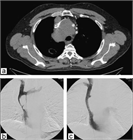

病態

1. 上大動脈症候群とは、上大静脈の閉塞や狭窄によって生じる上半身からの静脈血の還流障害により、静脈圧の上昇を来し、頭部、顔面、上肢、頚部および上半身のうっ血・浮腫を来す症候群である。

1. その原因として肺癌など胸部悪性疾患が多く、腫瘍に関連する救急疾患(Oncologic emergency)の1つに位置づけられている。